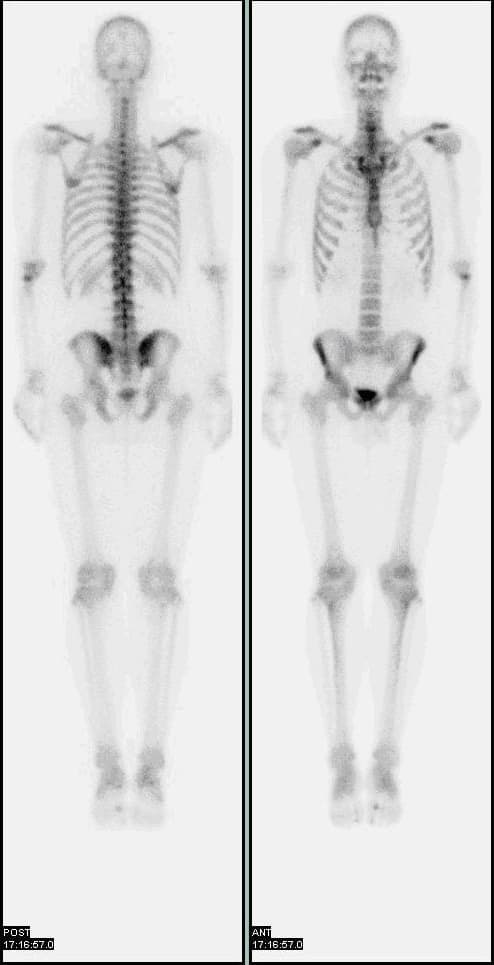

A bone scan or bone scintigraphy sɪnˈtɪɡrəfi is a nuclear medicine imaging technique of the bone. It can help diagnose a number of bone conditions, including cancer of the bone or metastasis, location of bone inflammation and fractures (that may not be visible in traditional s), and bone infection (osteomyelitis). Nuclear medicine provides functional imaging and allows visualisation of bone metabolism or bone remodeling, which most other imaging techniques (such as X-ray computed tomography, CT) cannot. Bone scintigraphy competes with positron emission tomography (PET) for imaging of abnormal metabolism in bones, but is considerably less expensive. Bone scintigraphy has higher sensitivity but lower specificity than CT or MRI for diagnosis of scaphoid fractures following negative plain radiography. Some of the earliest investigations into skeletal metabolism were carried out by George de Hevesy in the 1930s, using phosphorus-32 and by Charles Pecher in the 1940s. In the 1950s and 1960s calcium-45 was investigated, but as a beta emitter proved difficult to image. Imaging of positron and gamma emitters such as fluorine-18 and isotopes of strontium with rectilinear scanners was more useful. Use of technetium-99m (99mTc) labelled phosphates, diphosphonates or similar agents, as in the modern technique, was first proposed in 1971. The most common radiopharmaceutical for bone scintigraphy is 99mTc with methylene diphosphonate (MDP). Other bone radiopharmaceuticals include 99mTc with HDP, HMDP and DPD. MDP adsorbs onto the crystalline hydroxyapatite mineral of bone. Mineralisation occurs at osteoblasts, representing sites of bone growth, where MDP (and other diphosphates) "bind to the hydroxyapatite crystals in proportion to local blood flow and osteoblastic activity and are therefore markers of bone turnover and bone perfusion". The more active the bone turnover, the more radioactive material will be seen. Some tumors, fractures and infections show up as areas of increased uptake.